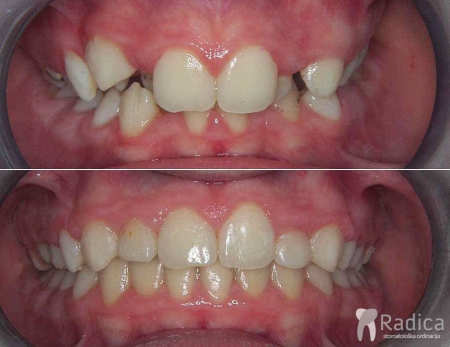

Kompresija – palatinalno položeni gornji lateralni sjekutići:

Kompresija – fiksni aparat, bez ekstrakcije: